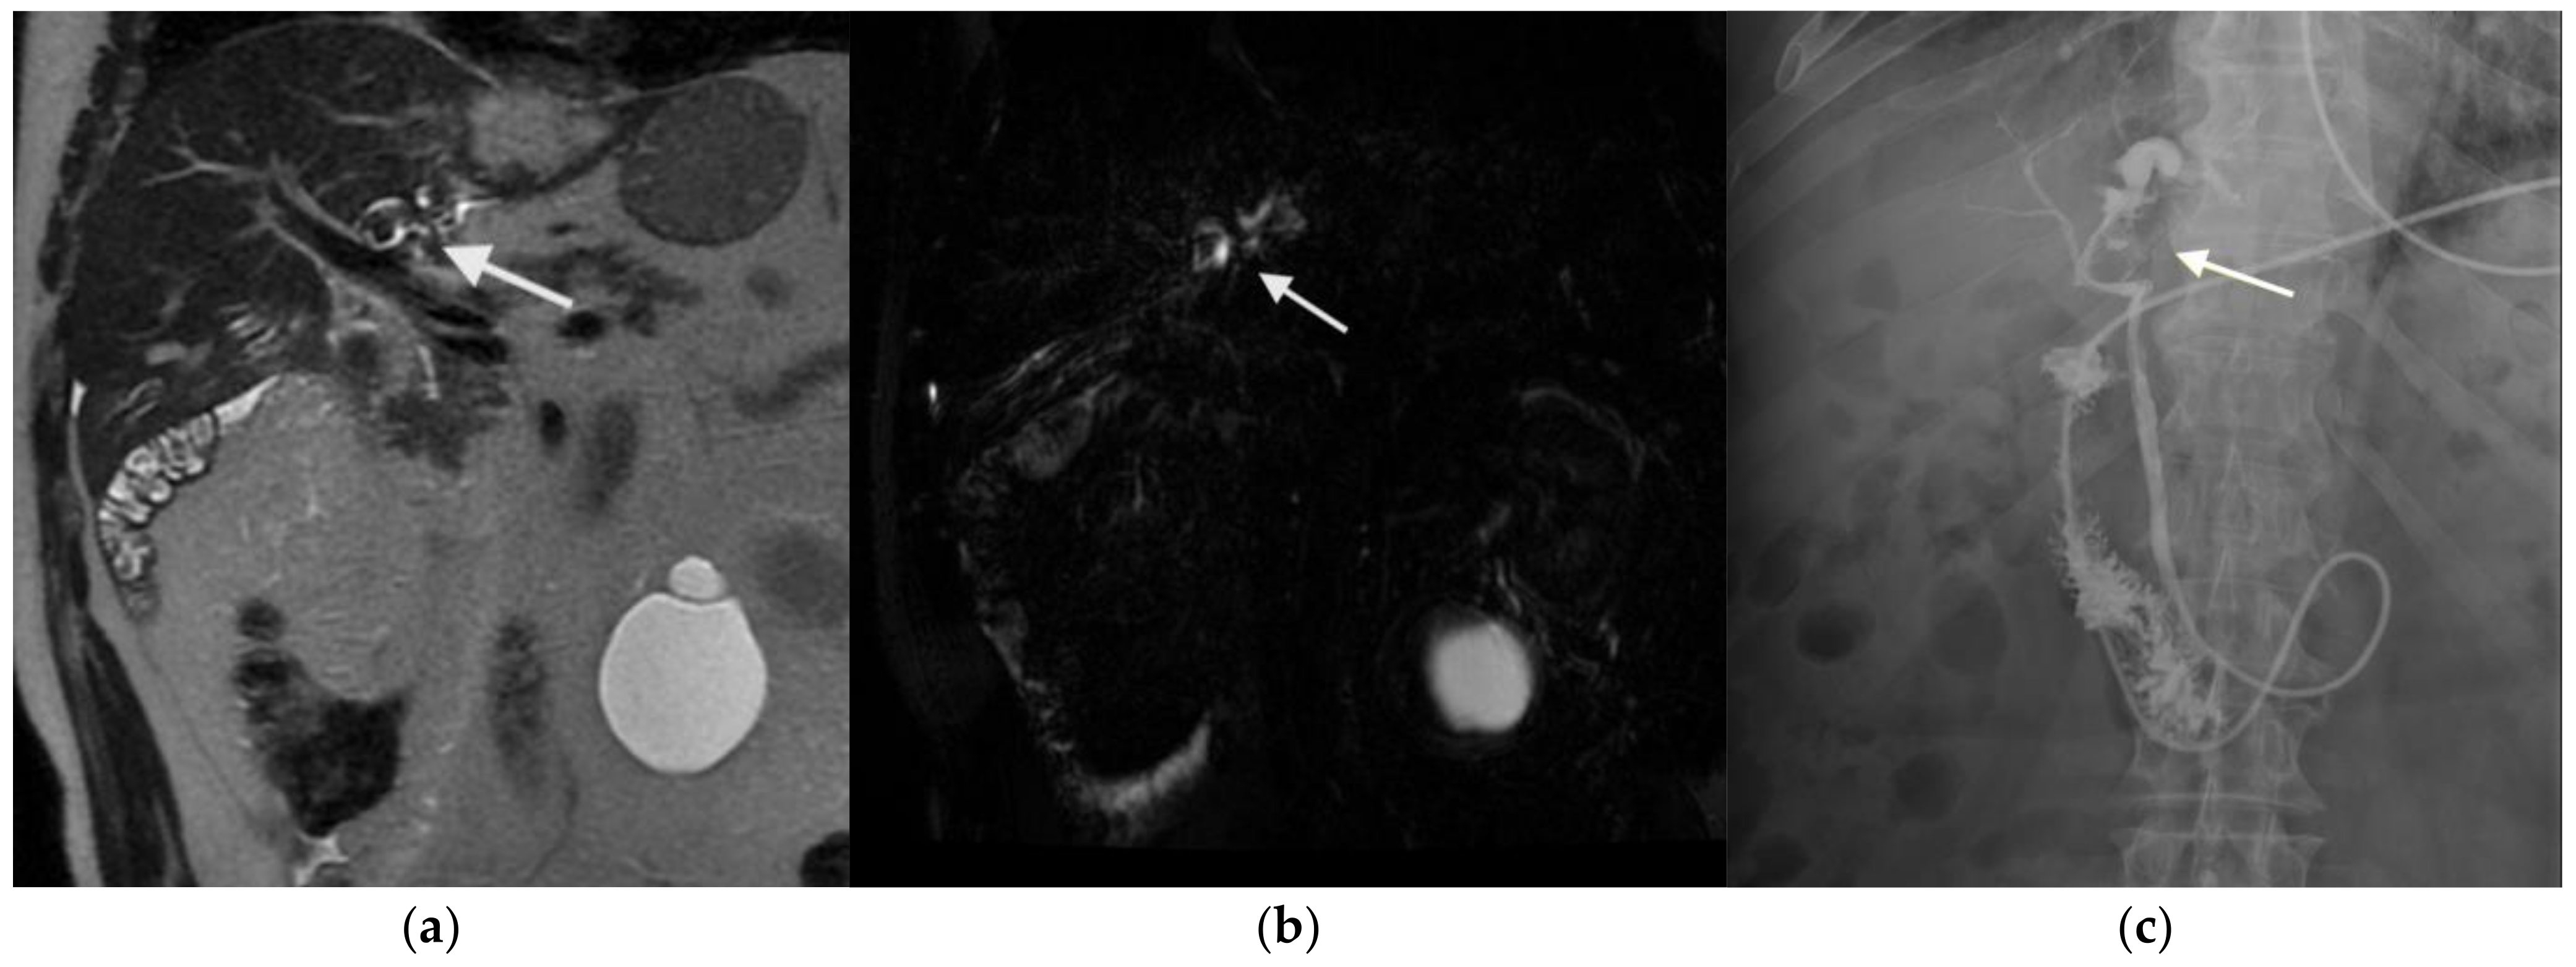

3.2. Figures, Tables, and Schemes